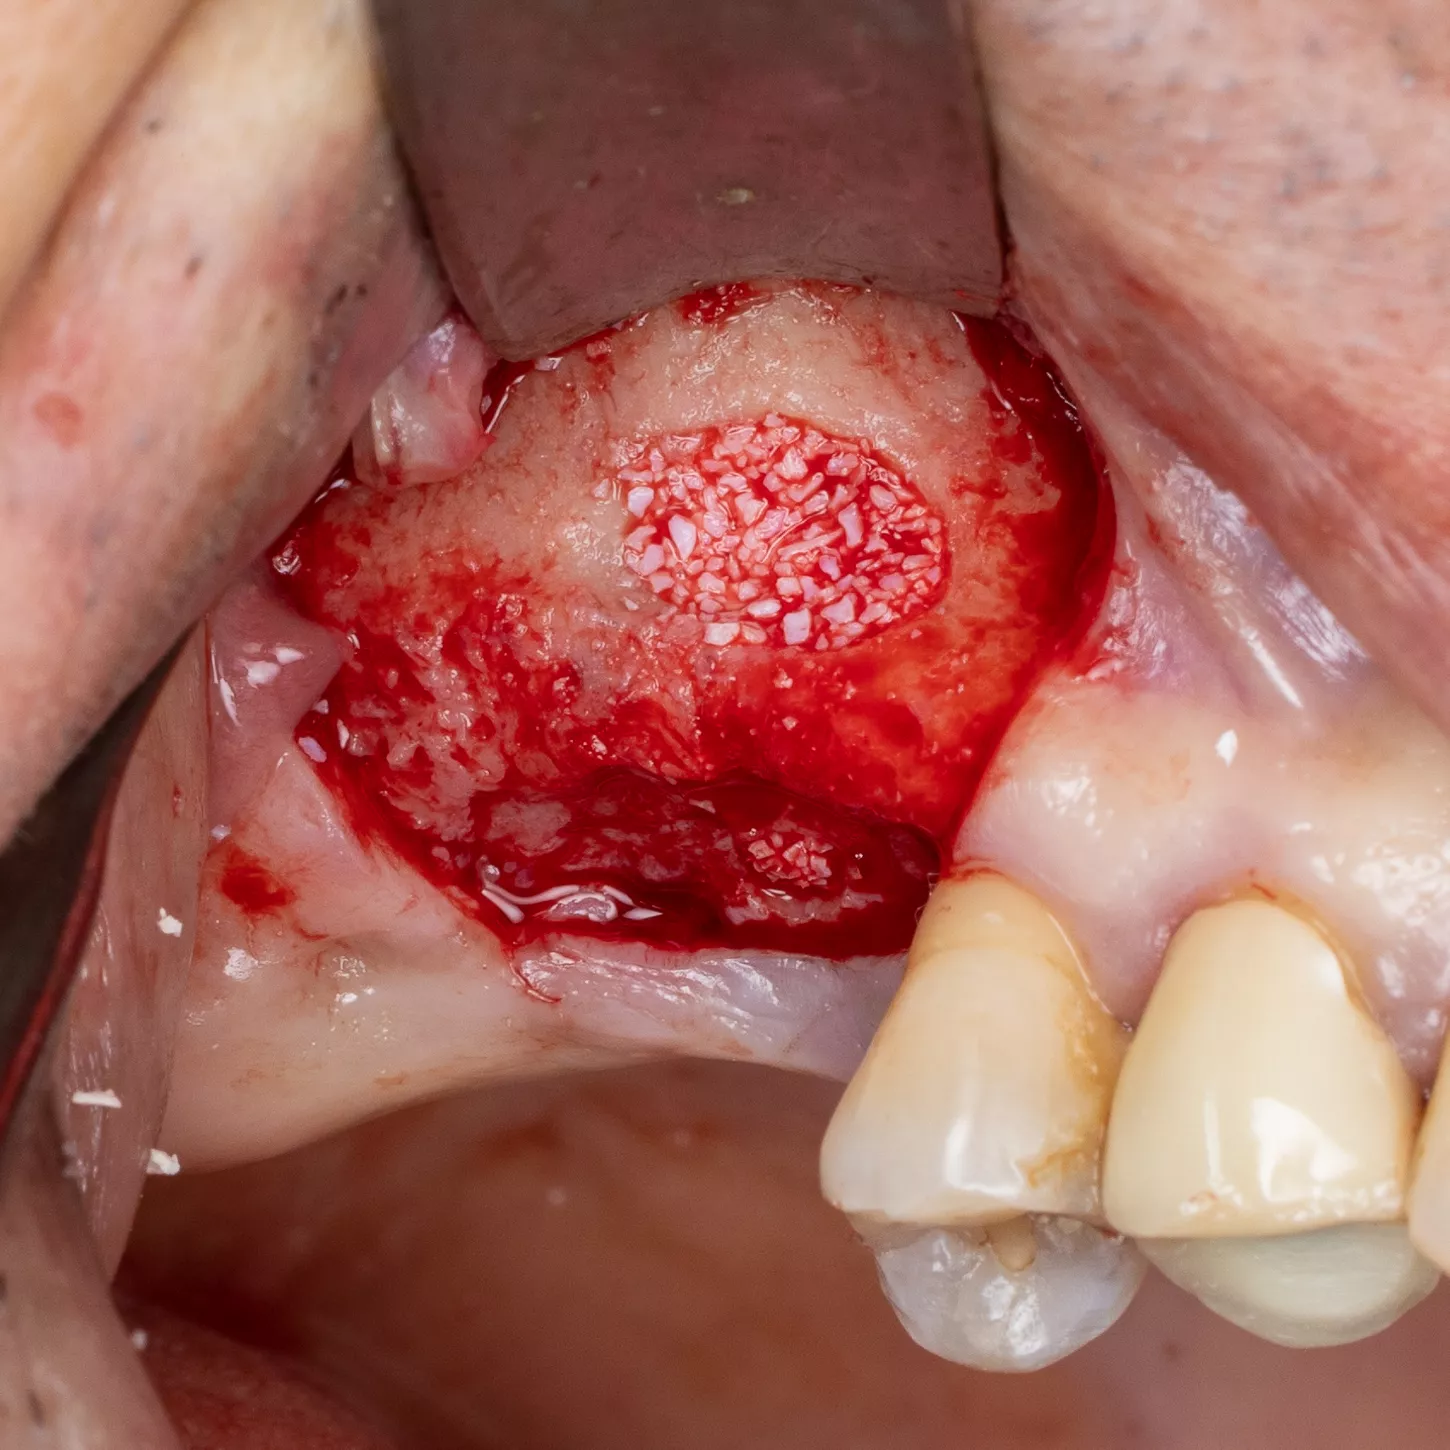

16. Prior to implant placement, filling of the palatal and mesial area of the sinus cavity with axenogenic biomaterial (XenoGraft, Straumann®).

17. Filling and compression using a graft packer in the mesio-palatal direction.

18. The sinus cavity is densely packed with the bone graft composite to support the implant.